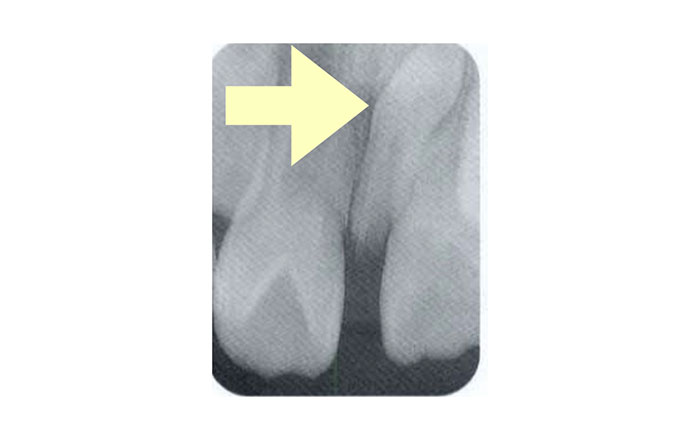

過剰歯が生えてくると、通常の歯に悪影響を与える場合があります。

過剰歯があることで歯並びを悪くさせる可能性があるため、基本は抜歯します。

抜歯しない場合でも、定期的にレントゲンを撮影し、悪影響を与えていないか確認を行っていきます。

その場合は、歯並びを含めた経過観察が必要となります。